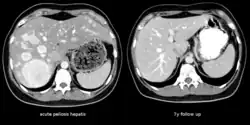

| The CT scan of a patient with peliosis hepatis (left): The follow-up CT (right) after 7 years shows full remission. | |

Peliosis hepatis is an uncommon vascular condition characterised by multiple, randomly distributed, blood-filled cavities throughout the liver. The size of the cavities usually ranges between a few millimetres and 3 cm in diameter.[1] In the past, it was a mere histological curiosity occasionally found at autopsies, but has been increasingly recognised with wide-ranging conditions from AIDS to the use of anabolic steroids. It also occasionally affects spleen, lymph nodes, lungs, kidneys, adrenal glands, bone marrow, and other parts of gastrointestinal tract.[2]

Treatment is usually directed towards management of the underlying cause. Withdrawal of azathioprine leads to remission in kidney transplant; bacillary peliosis responds to antibiotics. In rare circumstances partial resection of liver or transplant may be required.